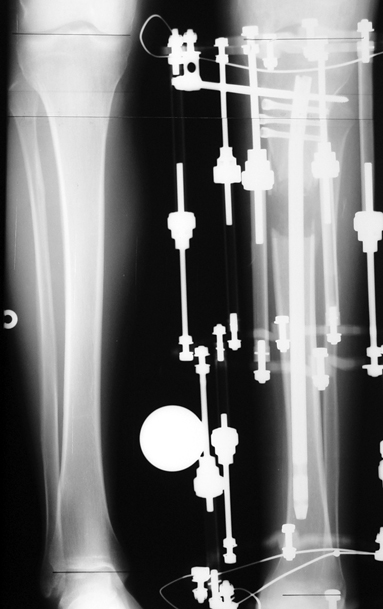

Patients with congenital lower limb shortness are hard cases who should be treated by surgeons experienced in lenghtening of developmental and posttraumatic lower limb shortness. Not only the amount of shortness is big but also it increases gradually and proportionately in time. A method to increase the growing rate of a short leg is not known. In addition to bone shortness, the soft tissues are thick and short, and they hinder lengthening by stretching. Development of the hip, knee and/or ankle joints may be insufficient and/or the joints may be instable. All of these factors shall be evaluated carefully to avoid irreversible damage in the joints, nerves and muscles. All cases of congenital lower limb shortness are treated in our department. In the beginning, we calculate how much length discrepancy there will be after skeletal maturity is gained. After all deformities and joint instabilities have been defined, the treatment stategy is organized for the limb, including the surgical correction of the hip, knee, ankle and foot. Lengthening surgery may involve one or more operations. Most of the patients with congenital lower limb shortness can be treated by lengthening and reconstruction. For most cases, we prefer to start lengthening and reconstruction procedures before the patient is 4 years old, usually before 2 years of age. An alternative treatment method is amputation so that the limb fits more easily in a prosthesis, and lengthening of the prosthesis with growing of the child in order to correct limb length inequality. We call this procedure prosthesis reconstruction surgery (PRS), and includes operations like Syme amputation and Van Ness rotationplasty. While this procedure may be the best choice for those patients with serious defects lacking one or more joints, in our opinion it is not the best choice fort he majority of patients. Our results for femur and tibia lengthening are perfect even for very big length differences, and perfect results are achieved in development and maintenance of joint functions.

This includs lower limb shortness which occurs following growth plate disruption and growth arrest, Ollier’s Disease, multiple osteochondomatosis, poliomyelitis, infection, radiation (radiotherapy), cerebral palsy, spina bifida, club foot and similar disorders. Additional abnormalities are frequent in this group. Many cases can be treated with one or two lengthening operations. If present, deformity can be corrected simultaneously with shortness. For condirtions that damage the hip joint at the first year of life like neonatal sepsis, we reconstruct the hip joint with pelvic support osteotomy in addition to lengthening, and a hip joint with nearly normal function is acquired.

3. POSTTRAUMATIC LOWER LIMB SHORTNESS (MALUNION)

This type of shortness occurs after a fracture heals in a shortened position. Most cases are seen in adults and can be treated with one lengthening operation. Additional deformities can be corrected simultaneously. Most of these cases can be treated with lengthening over nail or just corrections and intramedullary nailing.